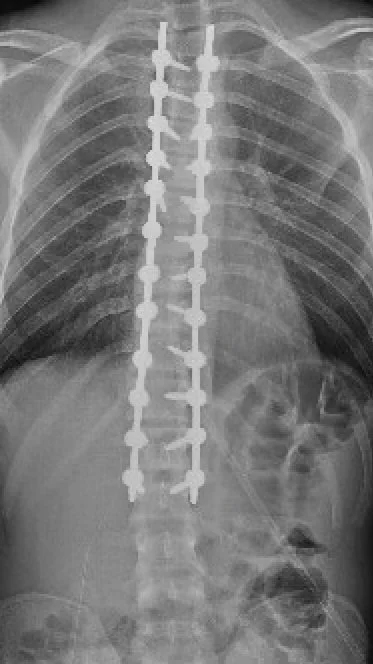

Severe kyphotic deformity

A very severe kyphotic deformity after spinal infection. There is a very sharp angulation in the spinal column.

Postop image showing corrected kyphotic curvature

After removing the diseased vertebrae, a more normal curvature was restored to the spine.